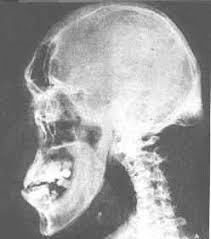

يمكن أن تتغير سحنة الوجه بشكل تدريجي كأن يبرز الفك السفلي و يتضخم الأنف و تثخن الشفتان و تنفرج المسافة بين الأسنان .. و نظرأً هذه الأعراض تتطور بشكل بطيء جداً لذا فقد يتأخر التشخيص لعدة سنوات .. و لعل البعض ينتبه لحالته الصحية عندما يطالع في ألبوم الصور و يقارن صورته الحالية مع صوره في السنوات القريبة الماضية

2. ملامح الوجه عريضة و كبيرة

3. بروز في الفك السفلي و بالتالي يلاحظ بروز الأسنان نحو الأمام